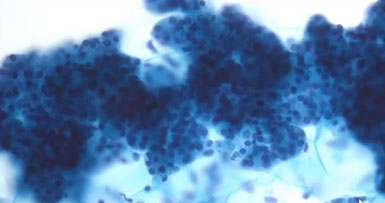

Acinic cell carcinoma

Acinic cell carcinoma

2nd MCC salivary gland malignancy in minor salivary glands in adults (up to 6% of all neoplasms and 1/5 malignancies); usually in the parotid gland of women in the 5th-6th decade

- well-circumscribed, slowly growing mass that is occasionally painful

Cellular smears c loosely cohesive polygonal bland serous acinar cells c eccentric nuclei in background of naked nuclei and lymphs

- abundant granular / vacuolated cytoplasm c indistinct cell borders, round uniform nuclei and small nucleoli c cytoplasm that is foamy to coarsely granular +/- psammoma bodies

- BVs can be seen in some clusters (perivascular tumor growth)

- may have intranuclear pseudoinclusions

- mits are infrequent

IHC: cells have PAS-(+) diastase-resistant zymogen granules in cytoplasm, keratin, alpha-1-antichymotrypsin, alpha amylosa, VIP, myoep markers, can have focal NE staining

Px: usually has late recurrences

DDx: normal parotid gland (tumors lack striated and interlovular ducts, lack lobular architecture)